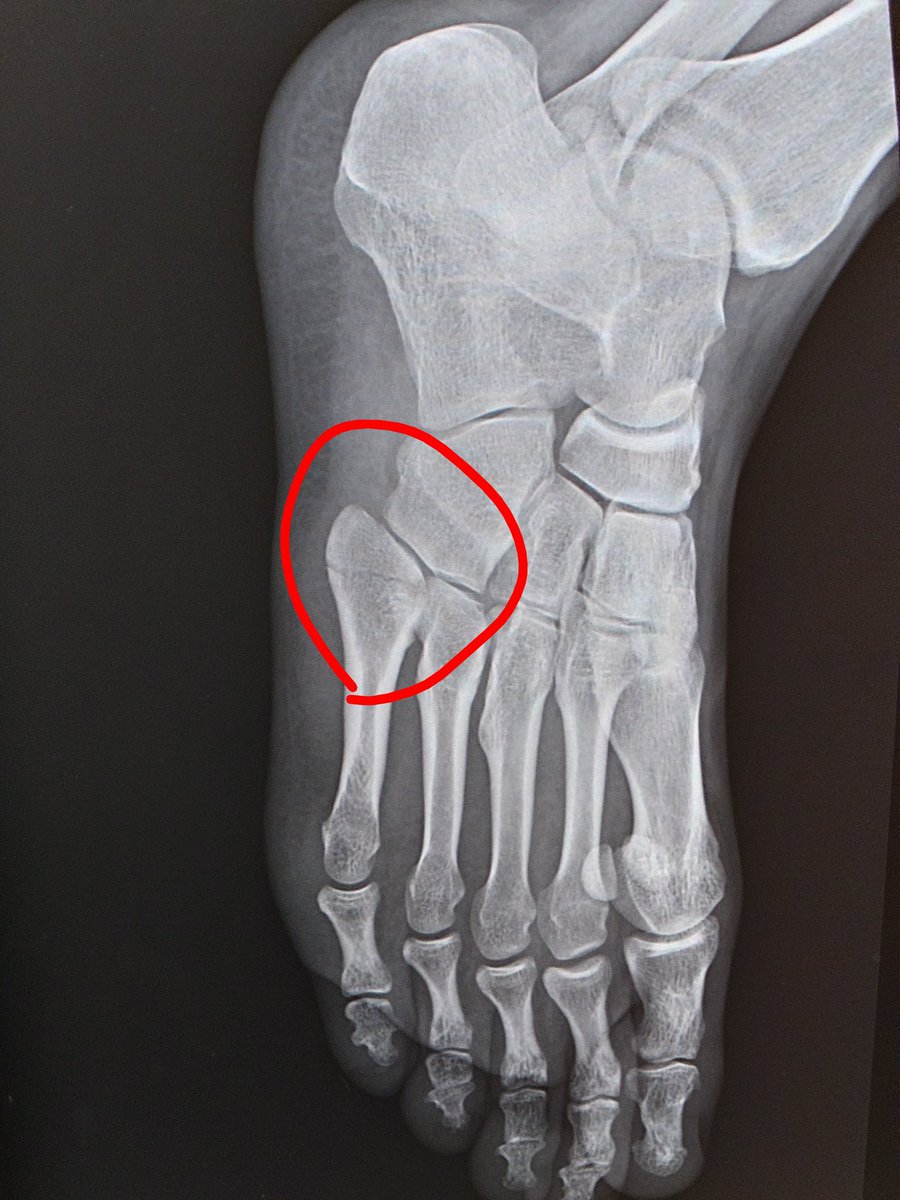

ポッキリ折れてる🤣

これ昨日のレントゲンなんですけどね。

救急の人とにこれ折れてない?って聞いたら血管じゃないか?って言われて、今日整形の人に聞くまでもなく診察室に入ったら、足固定ですね〜…長いGWになりそうだ🤣

救急で病院、骨折らしい。 まだ認めたくない🤣 明日改めて整形外科で診察。